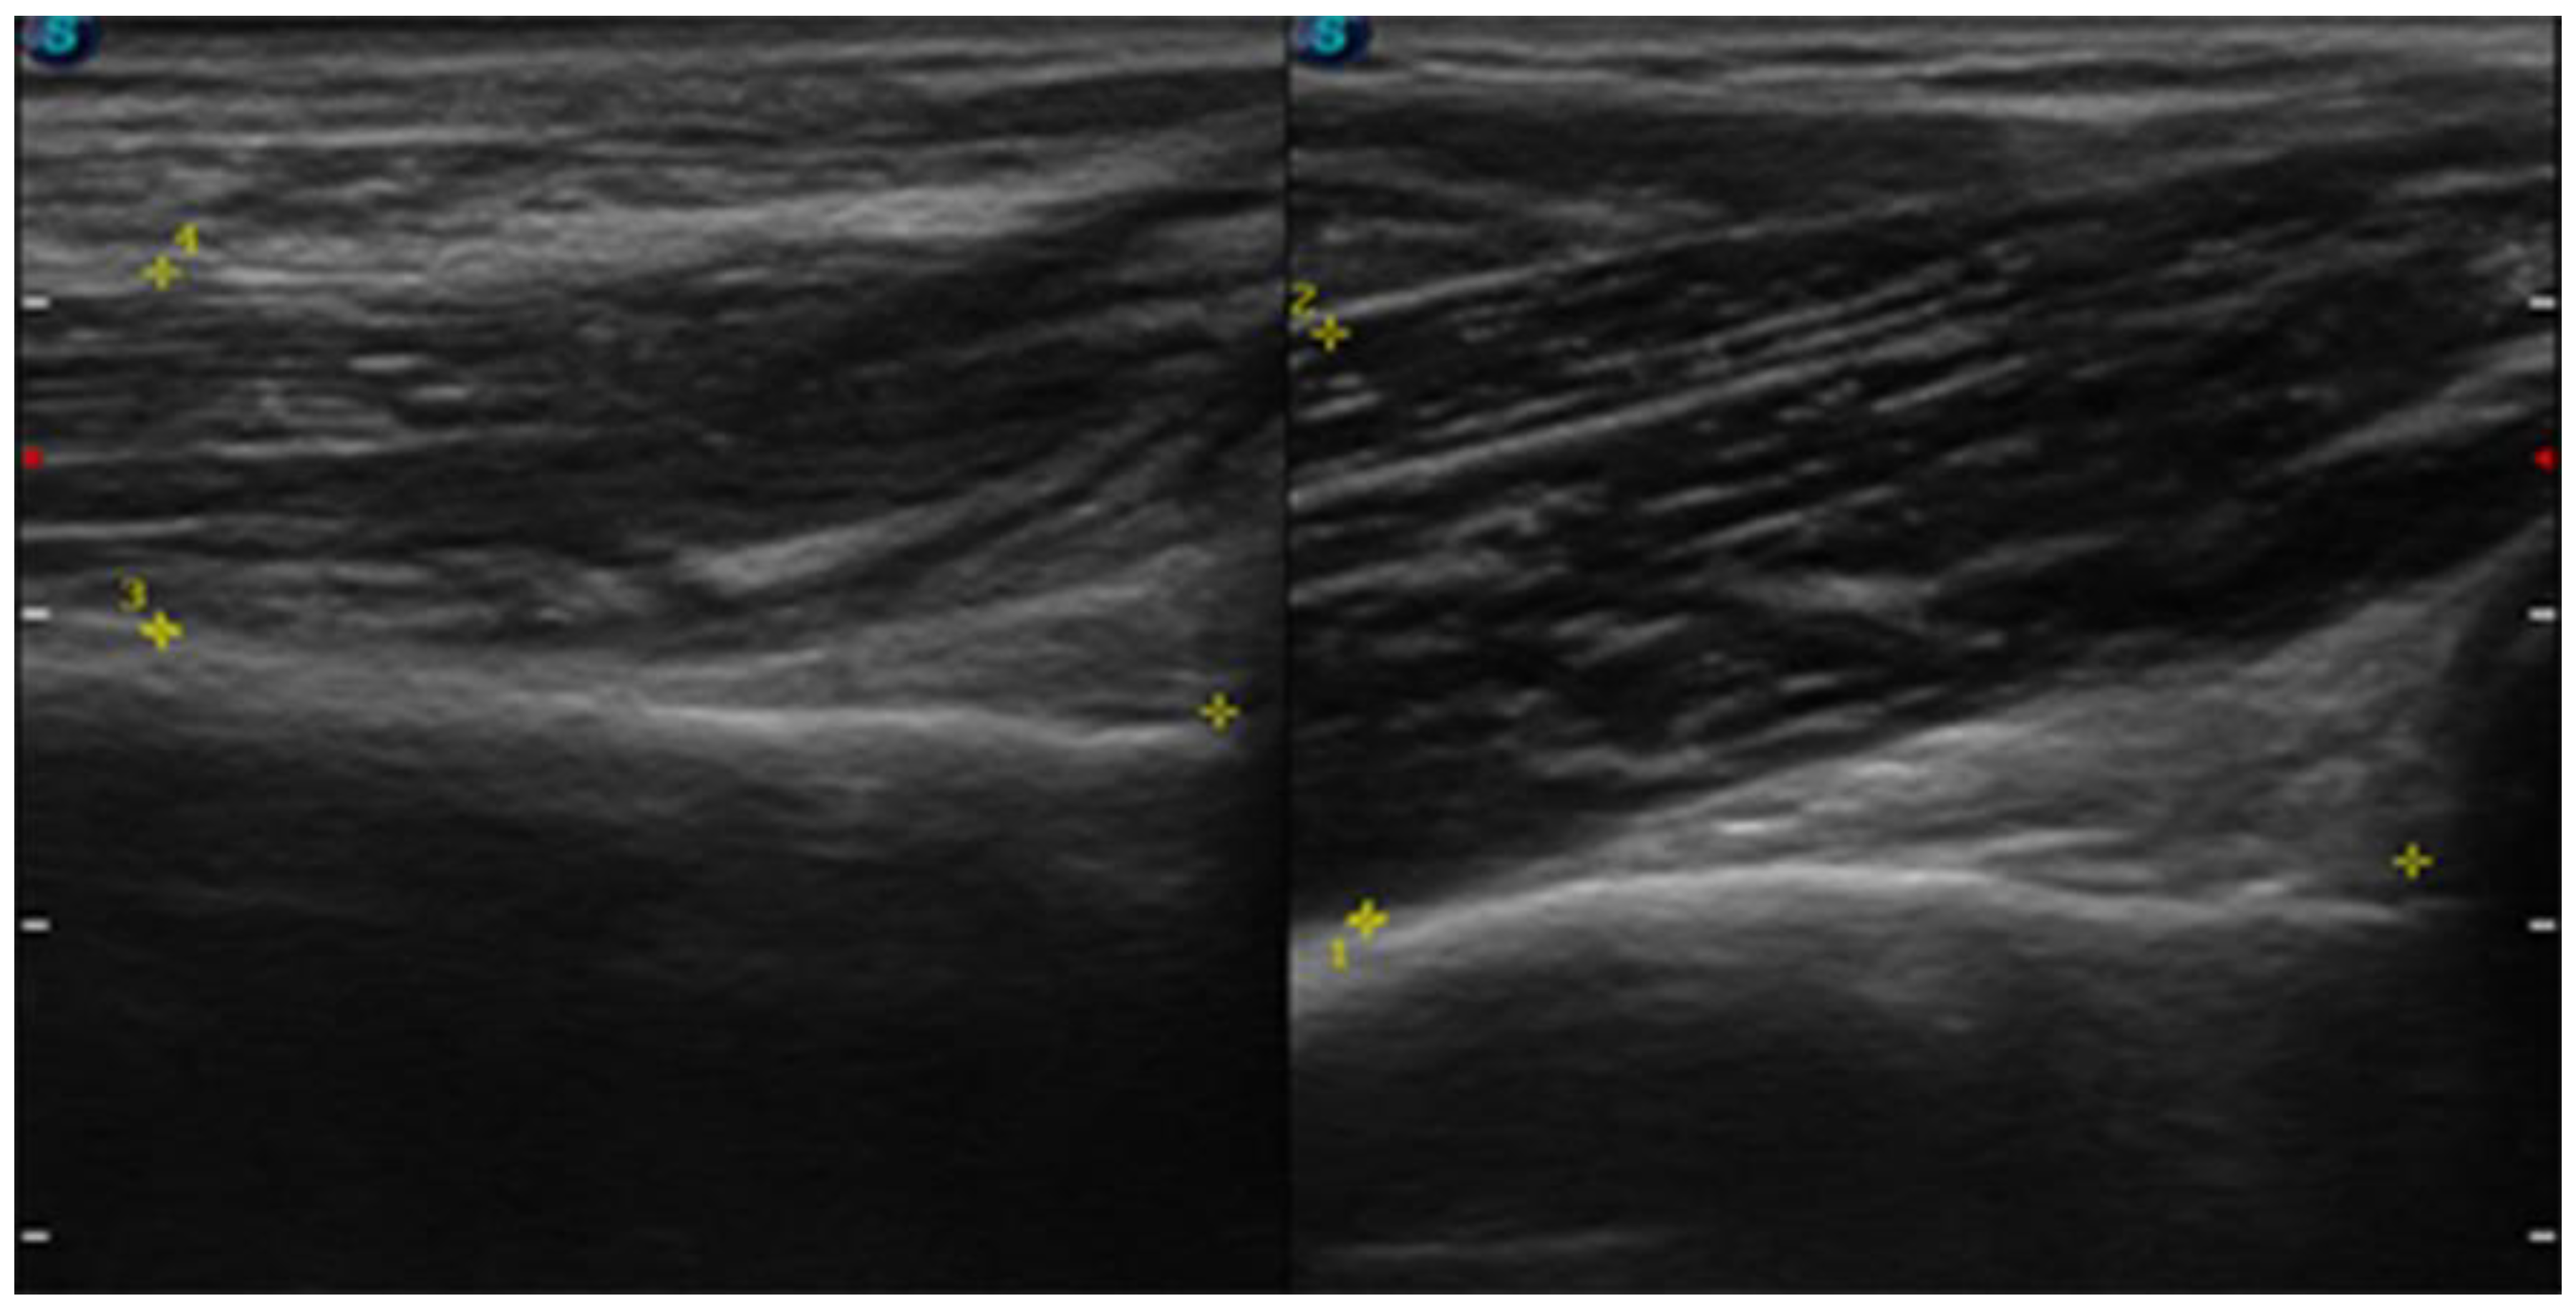

| July | Symptoms: brachialis muscle atrophy (Figure 1 and Figure 2) (pain 4/10 NPRS). Assessment: medical history, physical examination, ultrasound (orthopaedic surgeon). Diagnosis: unspecified soft tissue diseases associated with their use overload and overexertion (M70.9 ICD). Treatment: pharmacological treatment, avoid full weight-bearing. Effects: no positive therapeutic effect. |

| October | Symptoms: episodic of more severe pain, paraesthesia, tingling, numbness and burning sensations of right upper limb, (pain 3/10 NPRS). Assessment: medical history, physical examination (another orthopaedic surgeon), shoulder (Figure 3) and elbow MRI order (the same orthopaedic surgeon), cervical spine MRI order, electromyography, nerve conduction study (Table 2 and Table 3) (another orthopaedic surgeon), medical history, physical examination, ultrasound (another physiotherapist). Diagnosis: mononeuropathy of the upper limb, unspecified (G56.9 ICD) (orthopaedic surgeon), PTS suggestion (physiotherapist) Treatment: orthopedy surgeon: physiotherapy (massage, muscle relaxation, electrostimulation, exercises); physiotherapist recommendation: neurodynamic techniques. Effects: no positive effect. |

| CSA | affected | 0.09 cm2 | 0.06 cm2 |

| non-affected | 0.06 cm2 | 0.06 cm2 | |

| THss BM | affected | 11.61 mm | 11.77 mm |

| non-affected | 18.79 mm | 18.74 mm | |